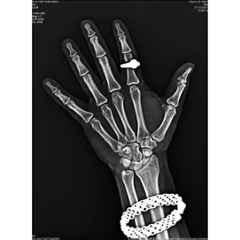

Spox A4 280 GSM Pet Inkjet Blue Medical Imaging Film delivers exceptional clarity and durability for precise medical imaging needs. With a sturdy 280 GSM thickness and A4 size, this film ensures reliable X-ray protection while maintaining sharp, vivid blue tones. Designed specifically for inkjet printers, it provides consistent, high-quality prints crucial for accurate diagnostics. Ideal for medical professionals seeking dependable accessories, this pack of 100 sheets combines performance and convenience, making it an essential addition to any healthcare setting. Trust Spox for reliable imaging film that supports effective treatment and patient care.